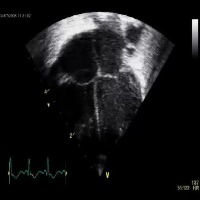

Healthcare and Medical Diagnostics: Utilize the "opt_subopt" model to analyze and categorize ultrasound images, helping medical professionals identify normal, abnormal, and suboptimal cases for better diagnosis and treatment planning.

Medical Education and Training: Integrate the computer vision model into medical education software and simulation tools, enabling students and healthcare practitioners to improve their skills in identifying and understanding different A4C classes in ultrasound images.

Quality Assurance for Ultrasound Equipment: Employ the "opt_subopt" model to evaluate the performance of ultrasound devices by identifying images with A4CSuboptimal and A4CAbnormal results, providing feedback to manufacturers for device improvements and maintenance.

Ultrasound Image Curation and Database Management: Implement the computer vision model in organizing large collections of ultrasound images based on their A4C classes, aiding researchers in finding specific categories of images more efficiently for their studies.

Telemedicine and Remote Consultations: Integrate the "opt_subopt" model with telemedicine platforms, allowing healthcare providers to review and analyze ultrasound images remotely and offer guidance to frontline staff in real-time based on the identified A4C classes.